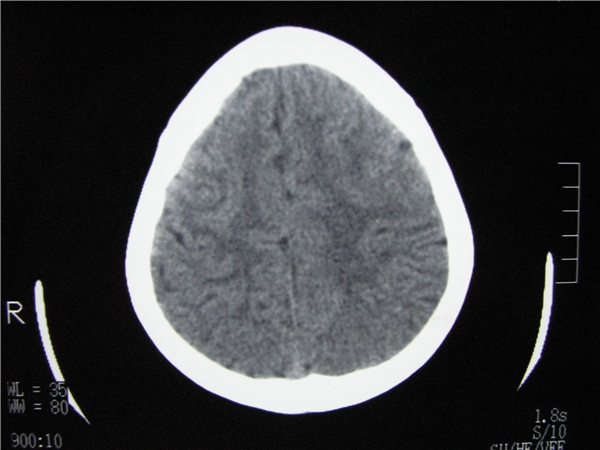

m 15y 头痛,以前有外伤史请老师看看除了囊肿还有别的吗?

蛛网膜囊肿。眼拙,看不出别的,倒是看到了双侧大脑中动脉影,类似“致密动脉征”。

双侧侧裂池和纵裂池近前颅窝蛛网膜囊肿。

无明显占位及负占位效应,考虑软化灶并脑室穿通畸形囊肿、局限性脑萎缩

蛛网膜囊肿,不能除外脑穿通畸形,支持。